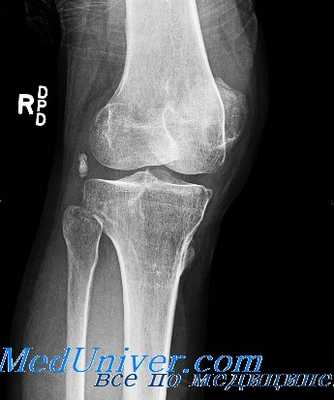

1. Состояние суставной щели. Суставная щель на снимке – это расстояние между костными суставными поверхностями (субхондральными пластинками). В норме суставная щель – параллельная полоса просветления разной величины в зависимости от того, какой сустав снят; чаще всего она составляет 1-5 мм. При патологических процессах происходит разрушение суставного хряща, суставная щель сужается (артриты и артрозы). Расширение суставной щели наблюдается при дефектах суставных концов (травма или воспаление), их деформациях (асептический некроз). Суставная щель может исчезнуть и наступит костный анкилоз, который определяется по переходу костных балок с одной суставной поверхности на другую.

2. Состояние субхондральных пластинок. В норме субхондральные пластинки чёткие и ровные, поверхности их конгруэнтны. Субхондральные пластинки могут быть неровными (деформирующий артроз, артрит) и нечёткими (воспалительные процессы). Также может быть наличие или отсутствие краевых костных разрастаний (артрозы).

3. Деформация и структура суставных поверхностей. Структура костной ткани суставных поверхностей может иметь литические или бластические очаги деструкции, склероз, пороз костной ткани. Далеко зашедшие патологические процессы приводят к деформациям суставных концов в целом (варусной и вальгусной, грибовидной и др.).